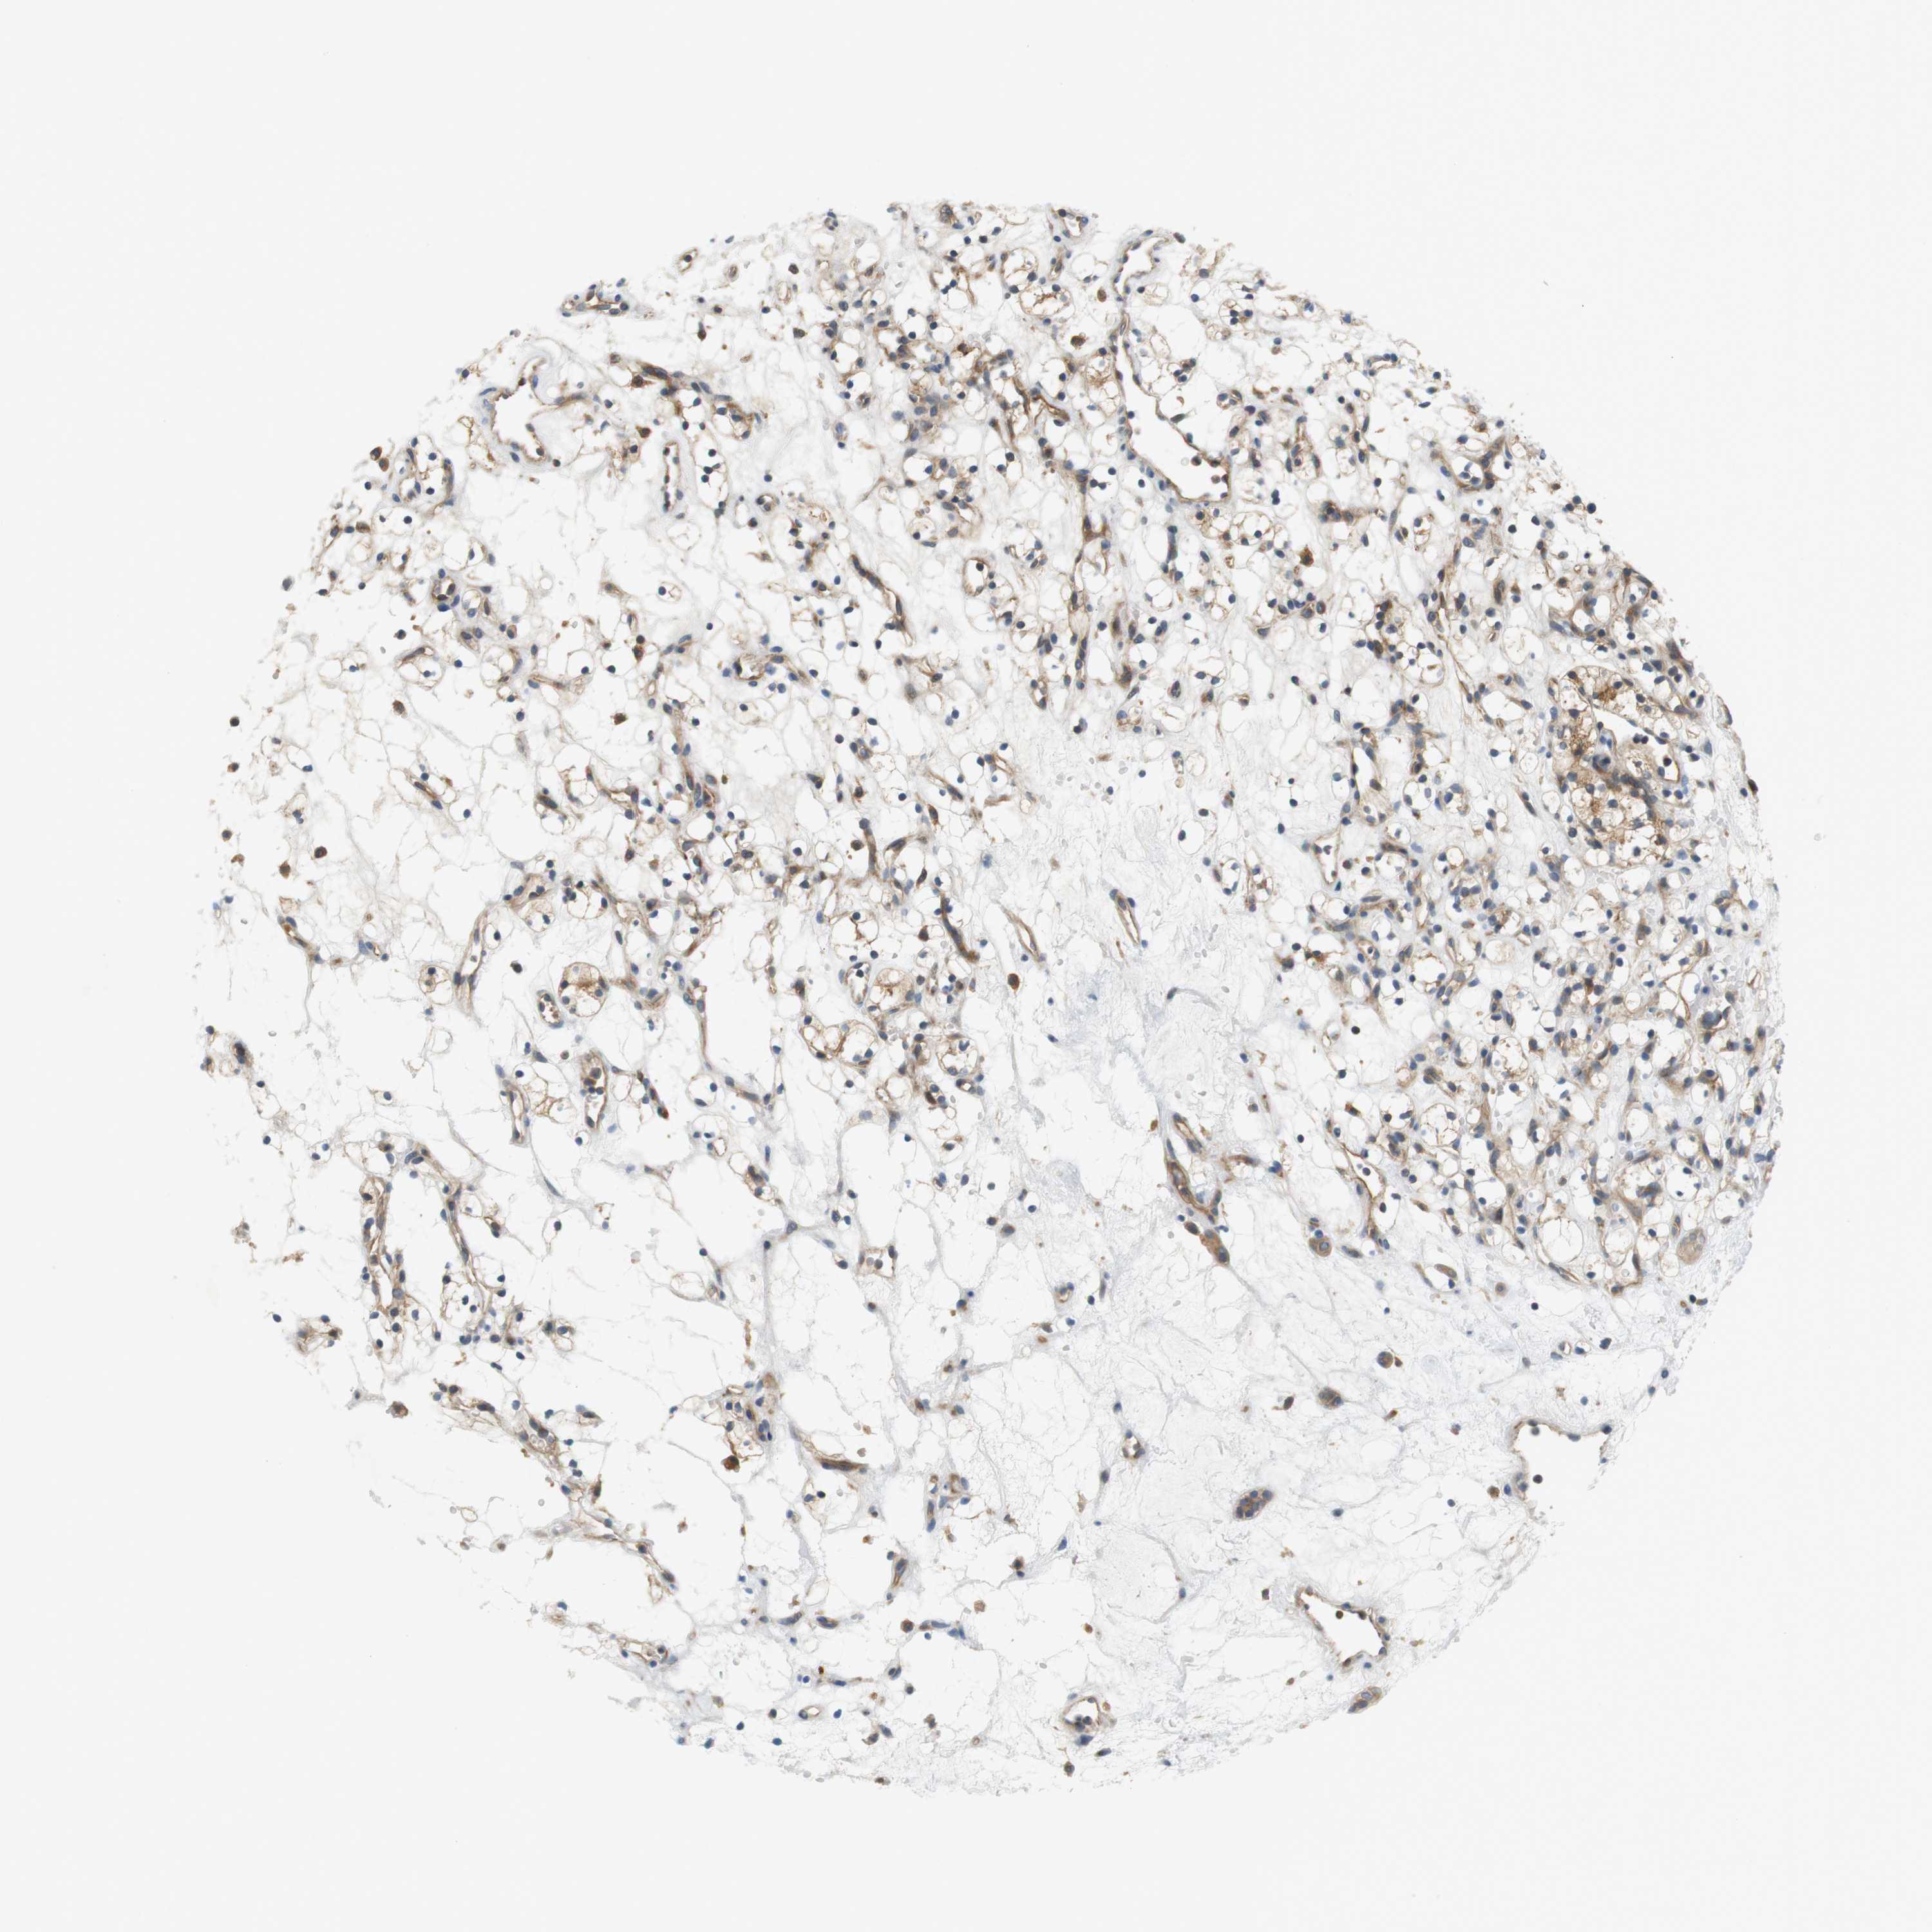

KIDNEY RENAL CLEAR CELL CARCINOMA (VALIDATION) - Interactive survival scatter ploti

The Survival Scatter plot shows the clinical status (i.e. dead or alive) for all individuals in the patient cohort, based on the same data that underlies the corresponding Kaplan-Meier plots. Patients that are alive at last time for follow-up are shown in blue and patients who have died during the study are shown in red.

The x-axis shows the expression levels (FPKM) of the investigated gene in the tumor tissue at the time of diagnosis. The y-axis shows the follow-up time after diagnosis (years). Both axes are complimented with kernel density curves demonstrating the data density over the axes. The top density plot shows the expression levels (FPKM) distribution among dead (red) and alive patients (blue). The right density plot shows the data density of the survived years of dead patients with high and low expression levels respectively, stratified using the cutoff indicated by the vertical dashed line through the Survival Scatter plot. This cutoff is automatically defined based on the FPKM cutoff that minimizes the p-score. The cutoff can be changed by dragging the vertical line or by entering a cutoff value in the square labeled "Current cut-off".

Under the Survival Scatter plot the p-score landscape (black curve; left axis) is shown together with dead median separation (red curve; right axis). Dead median separation is the difference in median mRNA expression between patients who have died with high and low expression, respectively. It is calculated as follows: median FPKM expression of dead patients with high expression - median FPKM expression of dead patients with low expression. This is intended to aid the user in visually exploring custom cutoffs and the associated p-scores and dead median separation.

Individual patient data is displayed and can be filtered by clicking on one or more of the category buttons on the top of the page. Categories describing expression level and patient information include: high, low, alive, dead, female, male and tumor stages. The scale of the x-axis can be toggled between linear and log-scale by clicking on the "x log" button. Mouse-over function shows TCGA ID, patient information and mRNA expression (FPKM) for each patient.

& Survival analysisi

Kaplan-Meier plots summarize results from analysis of correlation between mRNA expression level and patient survival. Patients were divided based on level of expression into one of the two groups "low" (under cut off) or "high" (over cut off). X-axis shows time for survival (years) and y-axis shows the probability of survival, where 1.0 corresponds to 100 percent.

SH3GLB1 is validated prognostic, high expression is favorable in Kidney Renal Clear Cell Carcinoma (validation)

Best expression cut offi

Based on the FPKM value of each gene, patients were classified into two groups and association between prognosis (survival) and gene expression (FPKM) was examined. The best expression cut-off refers the FPKM value that yields maximal difference with regard to survival between the two groups at the lowest log-rank P-value. Best expression cut-off was selected based on survival analysis .

When clicking on this number, the vertical dashed line indicating cut-off, the interactive survival plot, and the Kaplan-Meier curve will be adjusted to show results based on the best expression cut-off.

: 66.01

TCGA RNA samplesi

RNA-seq data is reported as average FPKM (number Fragments Per Kilobase of exon per Million reads), generated by the The Cancer Genome Atlas (TCGA) .

Normal distribution across the dataset is visualized with box plots, shown as median and 25th and 75th percentiles. Points are displayed as outliers if they are above or below 1.5 times the interquartile range. FPKM values of the individual samples are presented next to the box plot.

Average pTPM 75.2

Number of samples 100